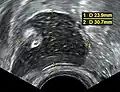

- Dermoid cyst in vaginal ultrasonography